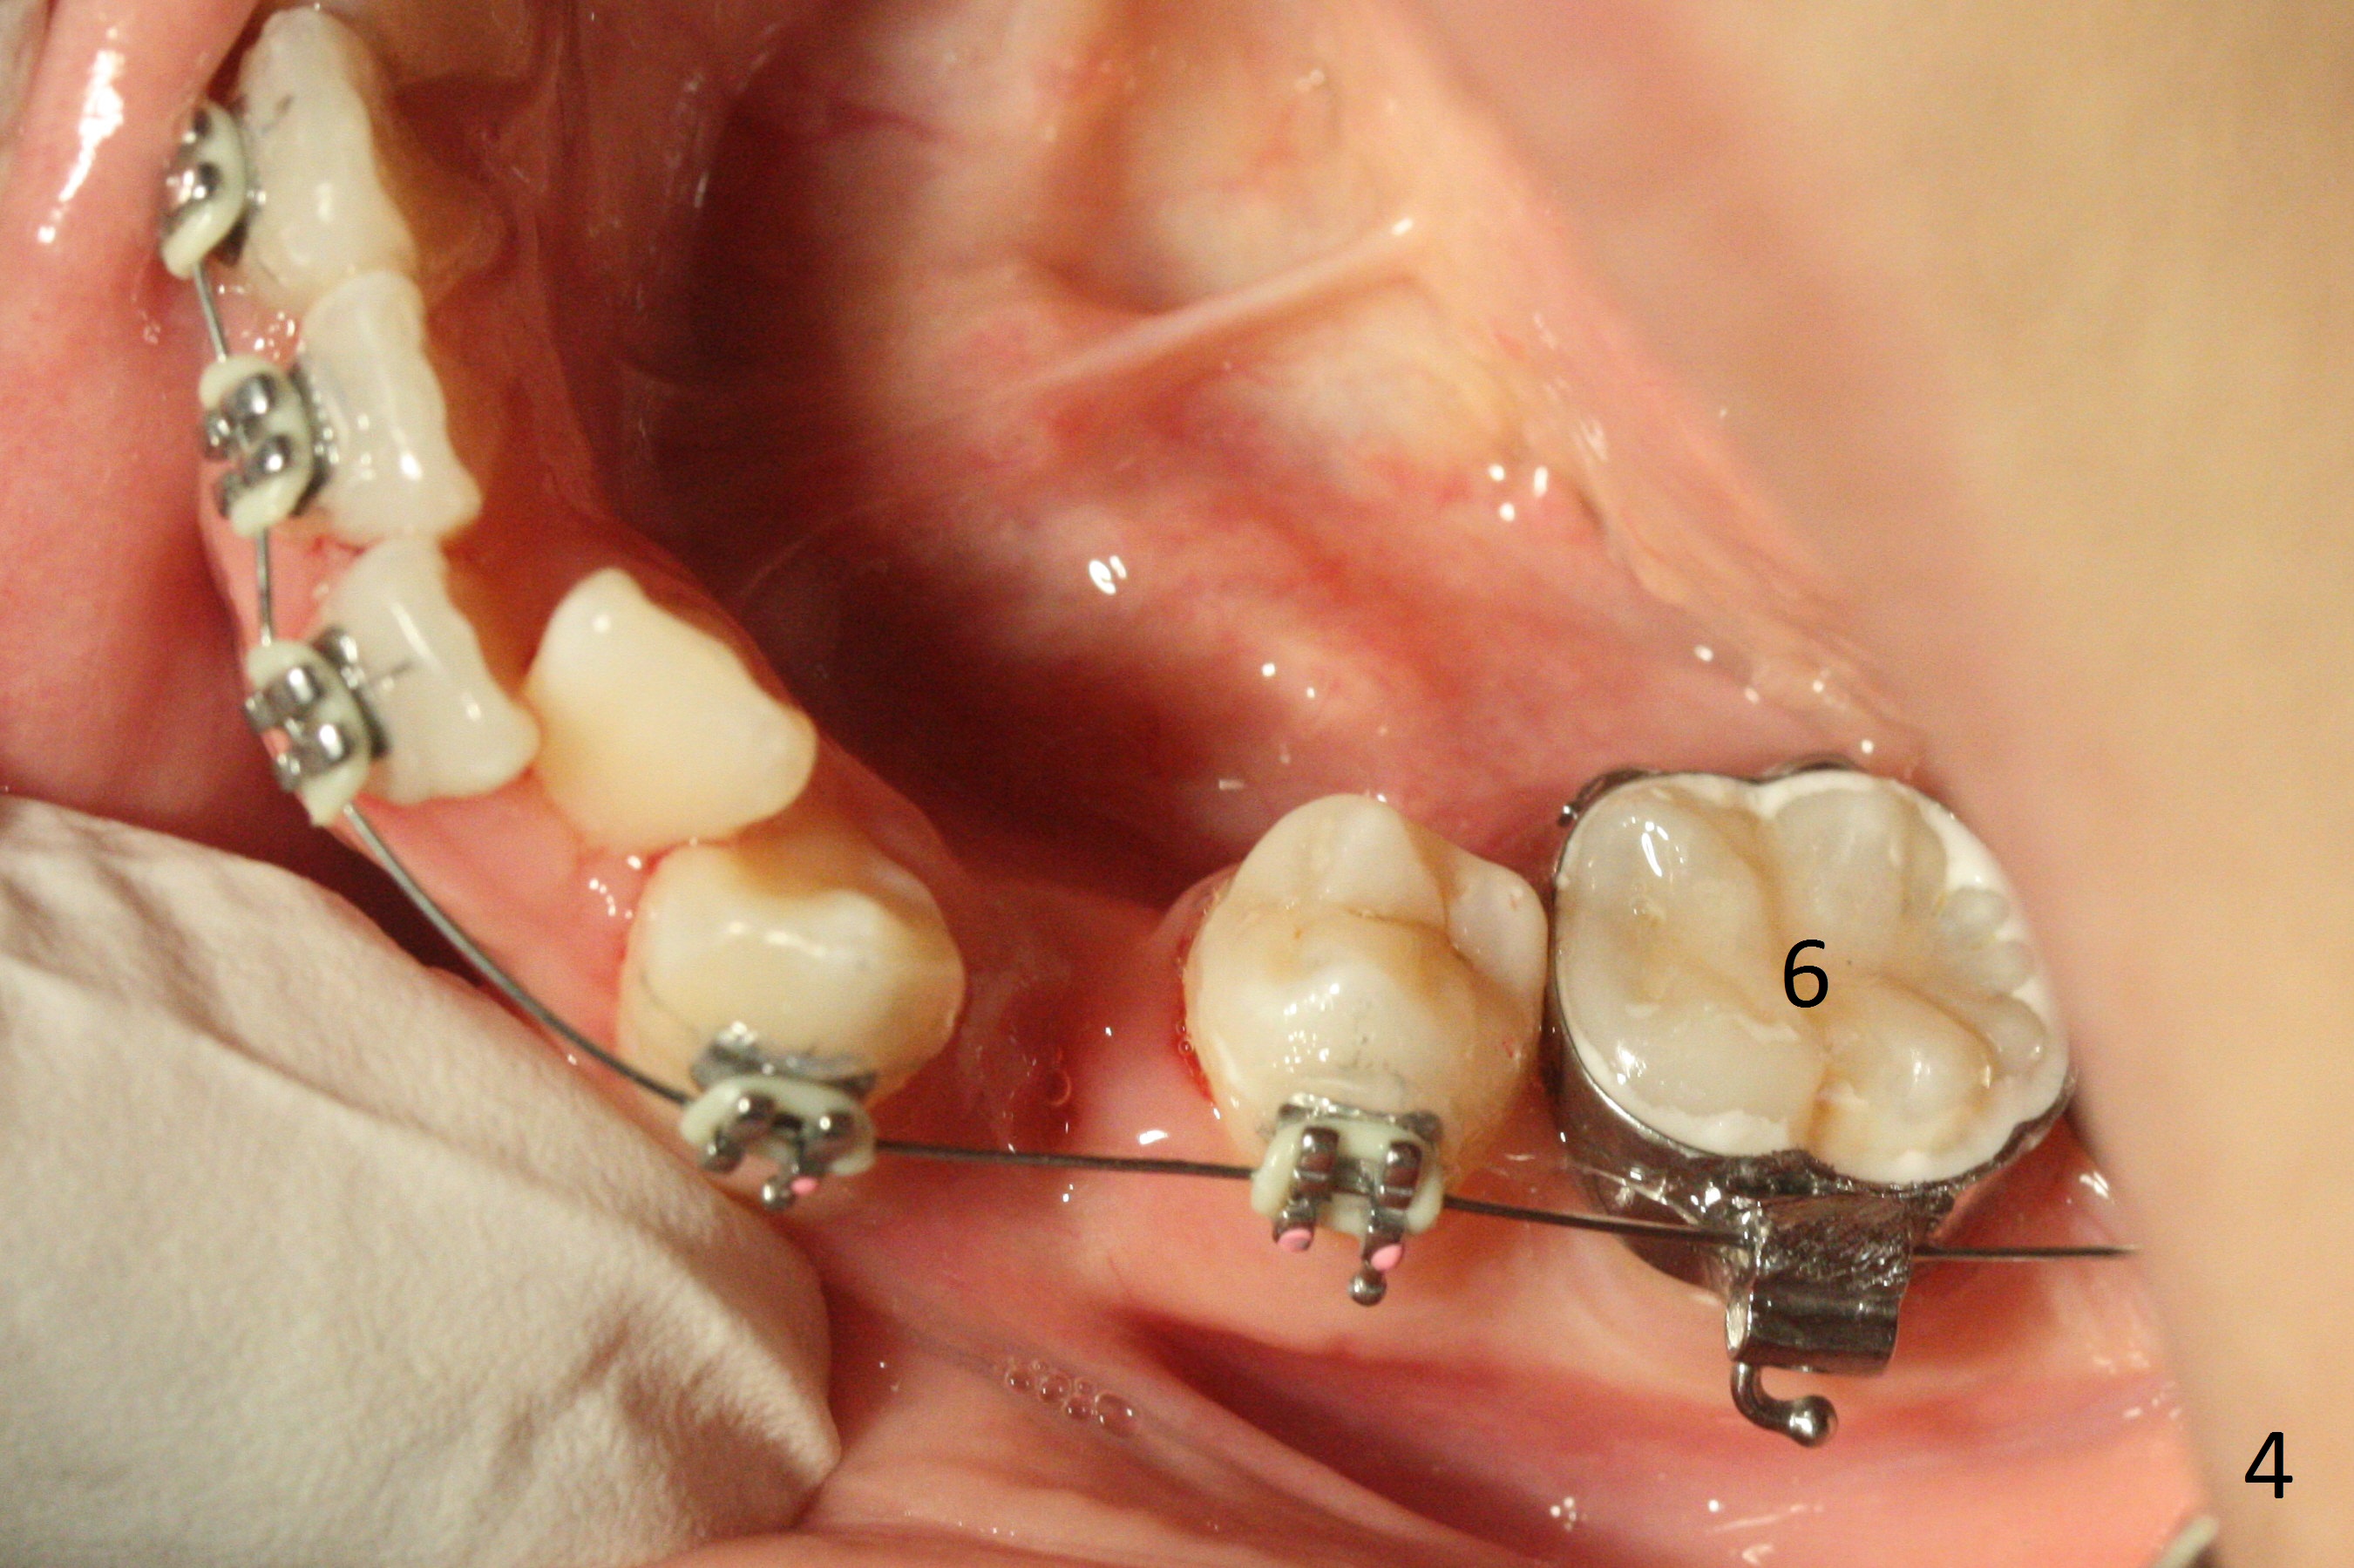

In fact there is enough space for banding at LL6 with reuse of 12 niti (Fig.4). Anterior crowding improves 1 month post banding (Fig.5, as compared to Fig.1-3); there is no difficulty in place 14 niti wire between UL 5 and 6 (Fig.6, as compared to Fig.3), since UL5 has been lingualzied.